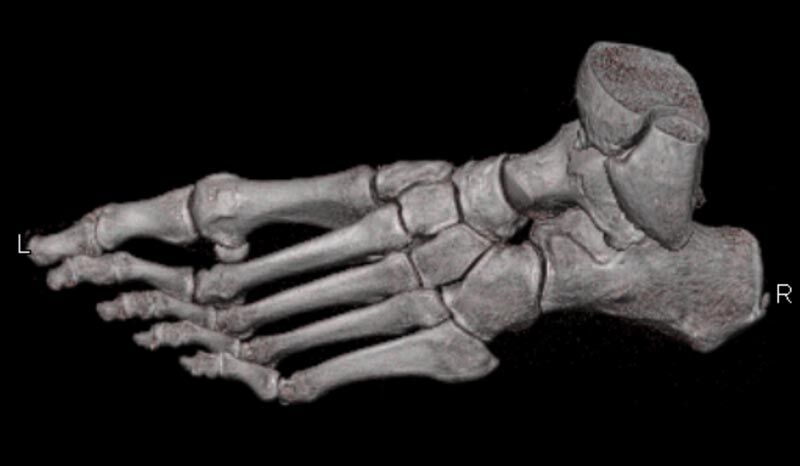

Extremitäten

• bei komplizierten Frakturen z. B. in der Nähe von Gelenken oder im Bereich der Handwurzel und Fußwurzel